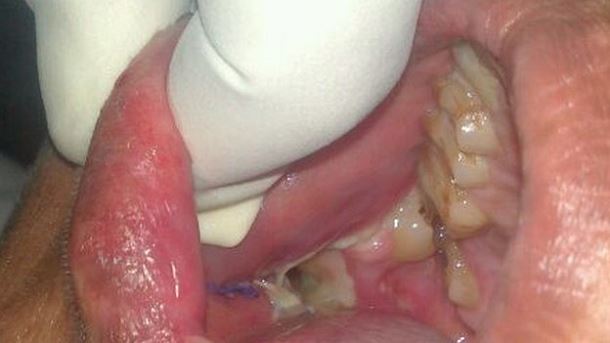

Cet adolescent, au lieu d’avoir 28 dents comme la plupart des gens en a 232 ! Ceci est due à une maladie rare appelée « odontome complexe » qui est caractérisée par de nombreuses dents à l’intérieur même des gencives de l’individu. Sa mâchoire avait tellement enflée qu’il s’est retrouvé dans l’obligation de faire appel à des médecins spécialisés… Il a été guéri mais apparemment certaines dents pourraient repousser plus tard ! Espérons pour lui que ce ne sera pas de si tôt…